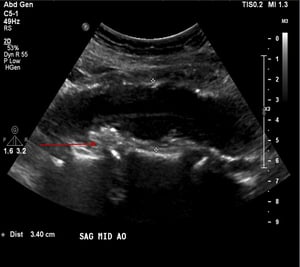

Aneurisma dell'aorta addominale (ecografia)

Questo paziente ha un aneurisma dell'aorta addominale che misura 3,4 cm (tra le croci bianche) nonché placca aterosclerotica o trombo murale (freccia rossa).

© 2017 Elliot K. Fishman, MD.